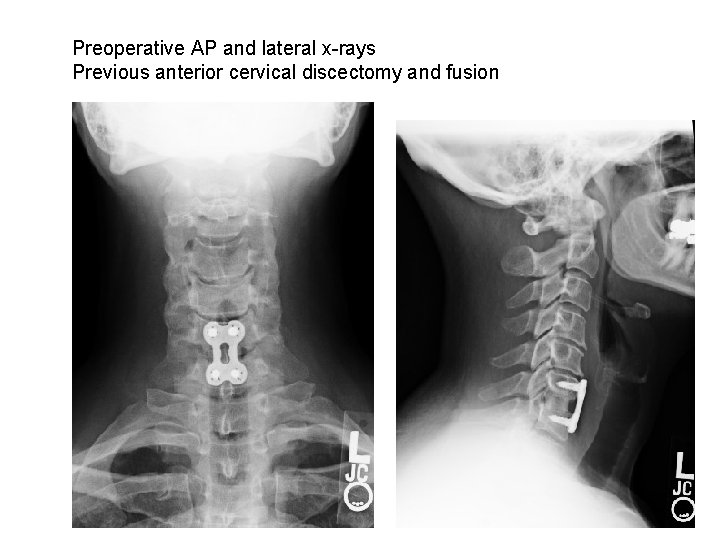

Preoperative AP and lateral x-rays Previous anterior cervical discectomy and fusion